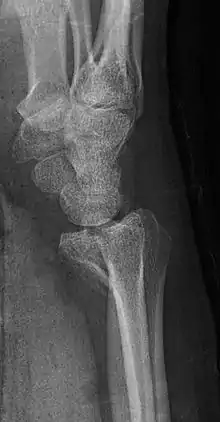

Lateral projectional radiograph of the same fracture.